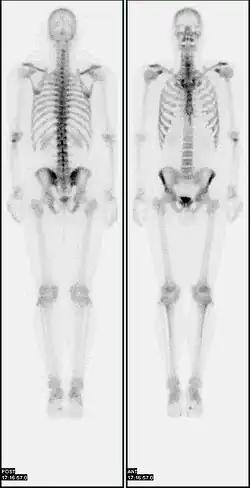

Bone scan showing multiple bone metastases from prostate cancer.